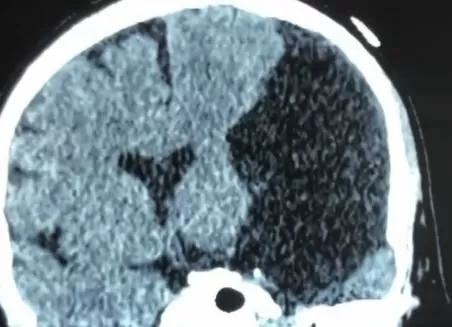

Арахноїдальні кісти середньої черепної ямки — це утворення мішочкоподібної форми в павутинній оболонці головного мозку, заповнені ліквором. Арахноїдальні кісти середньої черепної ямки головного мозкузазвичай носять доброякісний характер та є вродженими. У цьому випадку вони називаються первинними. Вторинні арахноїдальні кісти середньої черепної ямки можуть виникати після перенесених інфекційних захворювань головного мозку (менінгіти), після оперативних втручань, при синдромі Марфана, агенезії мозолистого тіла.

Серед арахноїдальних кіст середньої черепної ямки виділяють три типи: 1й тип – кісти невеликих розмірів, які знаходяться в межах середньої черепної ямки; 2й тип — кісти середніх розмірів, які виходять за межі середньої черепної ямки та розташовуються вздовж Сильвієвої щілини, зміщують скроневу долю; 3й тип — кісти великих розмірів тієї ж локалізації, але через свій розмір викликають зміщення скроневої, лобної та тім’яної долей мозку.

Основним методом діагностики арахноїдальної кісти середньої черепної ямки є МРТ головного мозку.